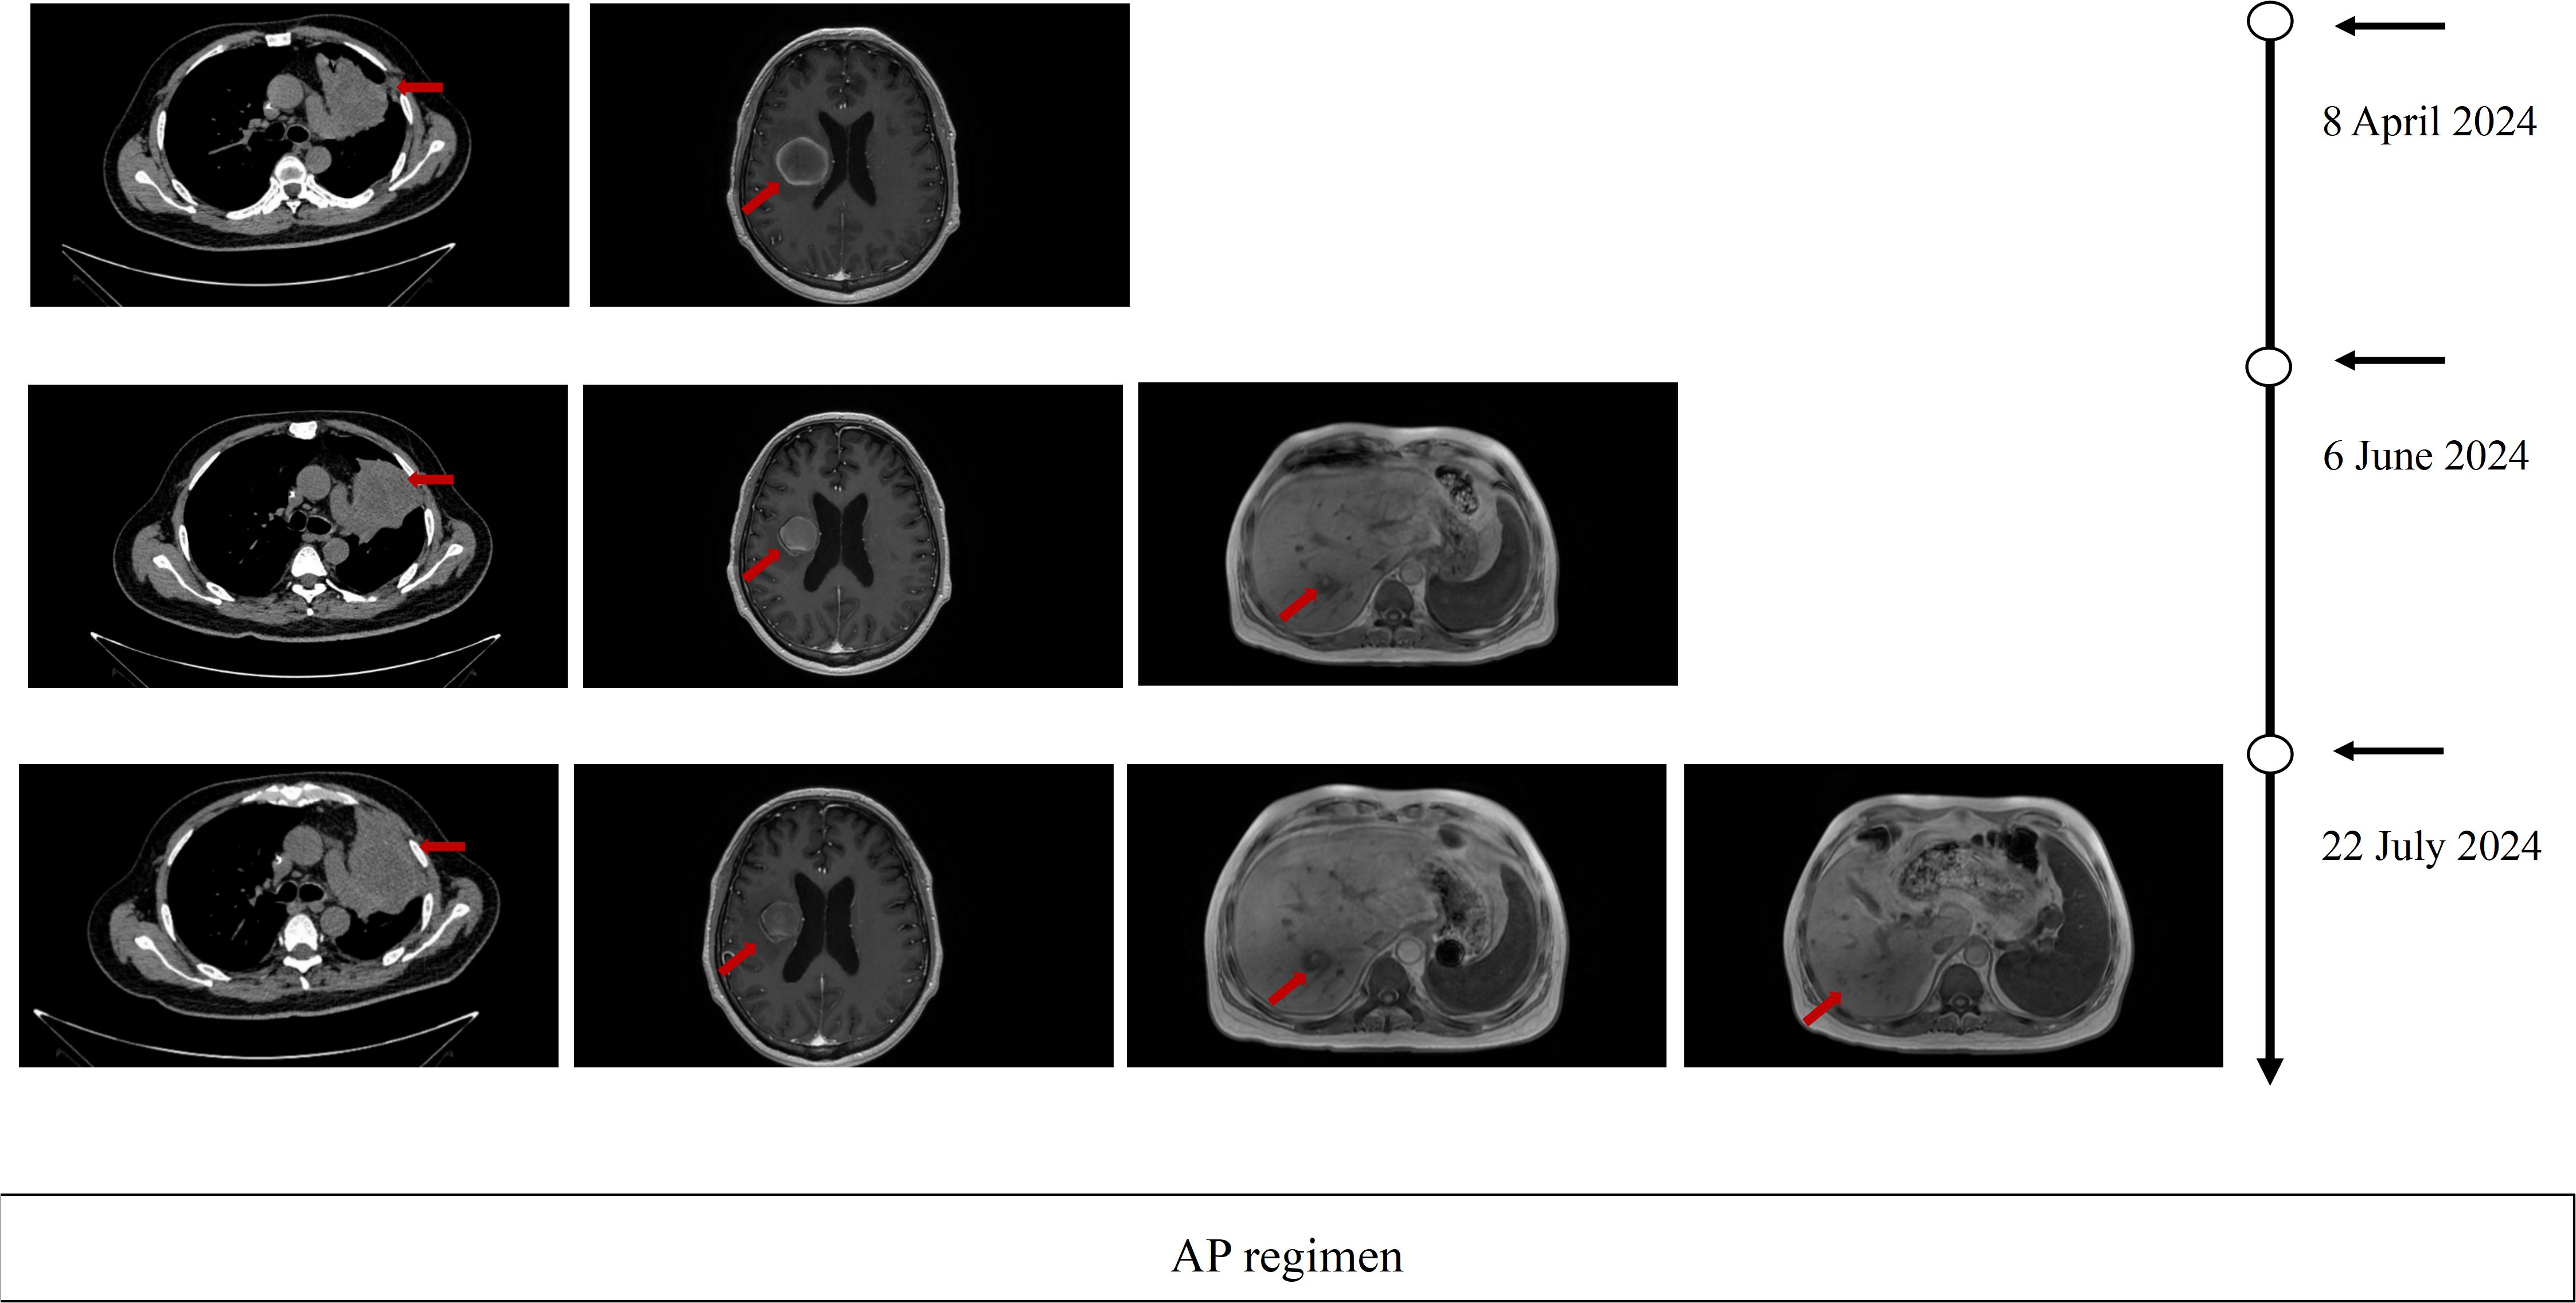

This case report describes a 51-year-old male with advanced Epidermal Growth Factor Receptor (EGFR) mutant (p.T790M and p.L858R) lung adenosquamous carcinoma who achieved a rapid partial response (PR) to ivonescimab monotherapy following progression on multi-line therapies, including third-generation EGFR-tyrosine kinase inhibitors (EGFR-TKIs), platinum-based chemotherapy, anti-angiogenic therapy, and immune checkpoint inhibitors. Despite initial responses to first-line firmonertinib-based combination therapy, progression-free survival (PFS) 13 months, the patient developed sequential resistance to subsequent regimens, including liver/brain metastases and treatment-related toxicities. After fourth-line therapy failure and severe intolerance to albumin-bound paclitaxel and bevacizumab, two cycles of ivonescimab—a first-in-class programmed cell death protein receptor-1 (PD-1)/vascular endothelial growth factor-A (VEGF-A) bispecific antibody—induced significant regression of pulmonary target lesions (PR), sustained over six cycles with minimal toxicity. This case highlights ivonescimab's dual-mechanism potential to overcome resistance in EGFR-mutant Non–small cell lung cancer (NSCLC) by concurrently alleviating PD-1-mediated immunosuppression and VEGF-driven angiogenesis. The observed efficacy in a low PD-L1 expression, tumor proportion score (TPS) 5%, tumor protein 53 (TP53)-co-mutated, and adenosquamous histology context aligns with prior clinical trial data (HARMONi-A/2), suggesting broad applicability across heterogeneous subgroups. While the rapid PR and favorable safety profile are promising, longer follow-up is required to assess durability and survival benefits. These findings underscore the need for further investigation of bispecific antibodies in precision oncology paradigms for multi-refractory EGFR-driven NSCLC.